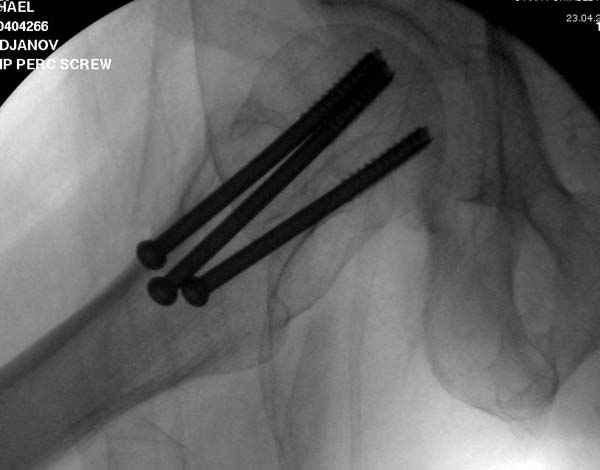

Re: неполный перелом шейки

Профилактику дальнейшего раскола неполного перелома шейки провели тремя канюлированными шурупами.